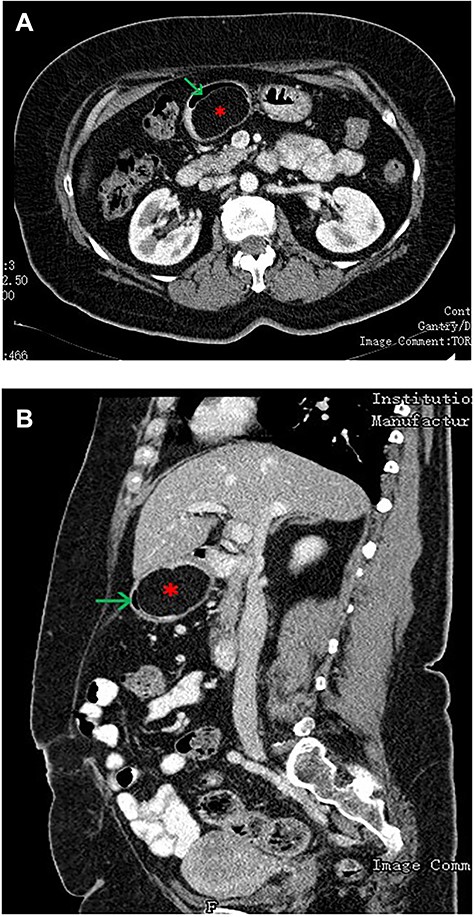

(A—coronal plane; B—sagittal plane): CT scan of the abdomen showing a large well-encapsulated and fat-attenuated submucosal lesion (8 × 3 cm) in the posterior wall of the gastric antrum, which causes lumen obstruction (*gastric lipoma, arrow—gastric lumen).

An upper GI endoscopy revealed a large subepithelial mass arising from the posterior wall of the gastric antrum, occupying more than 50% of the lumen, soft when pressed with biopsy forceps. The biopsies were non-diagnostic. Additionally, a contrast-enhanced computed tomography (CT) demonstrated a well-defined lesion of the antrum, measuring 8 × 3 cm, non-contrast enhancing and with uniform adipose density, highly suggestive of lipoma (Fig. 1). Endoscopic ultrasound (EUS) also showed a homogeneous and hyperechoic lesion limited to the submucosa (Fig. 2), supporting lipoma diagnosis.

Abdominal CT is the imaging study of choice and highly specific. In the case of gastric lipoma, it strongly suggests the diagnosis by visualization of a well-circumscribed homogeneous mass with fat density ranging between −80 and −120 Hounsfield units. These values are considered pathognomonic and suggest a diagnosis of gastric lipoma, by falling in the expected value range for adipose tissue [4, 5]. EUS is another useful imaging study to confirm the hypothesis of gastric lipoma. By EUS, gastric lipomas appear as homogeneous and hyperechoic lesions from the third layer of the gastric wall [7, 10]. Our patient was diagnosed on endoscopy and confirmed with CT and EUS.